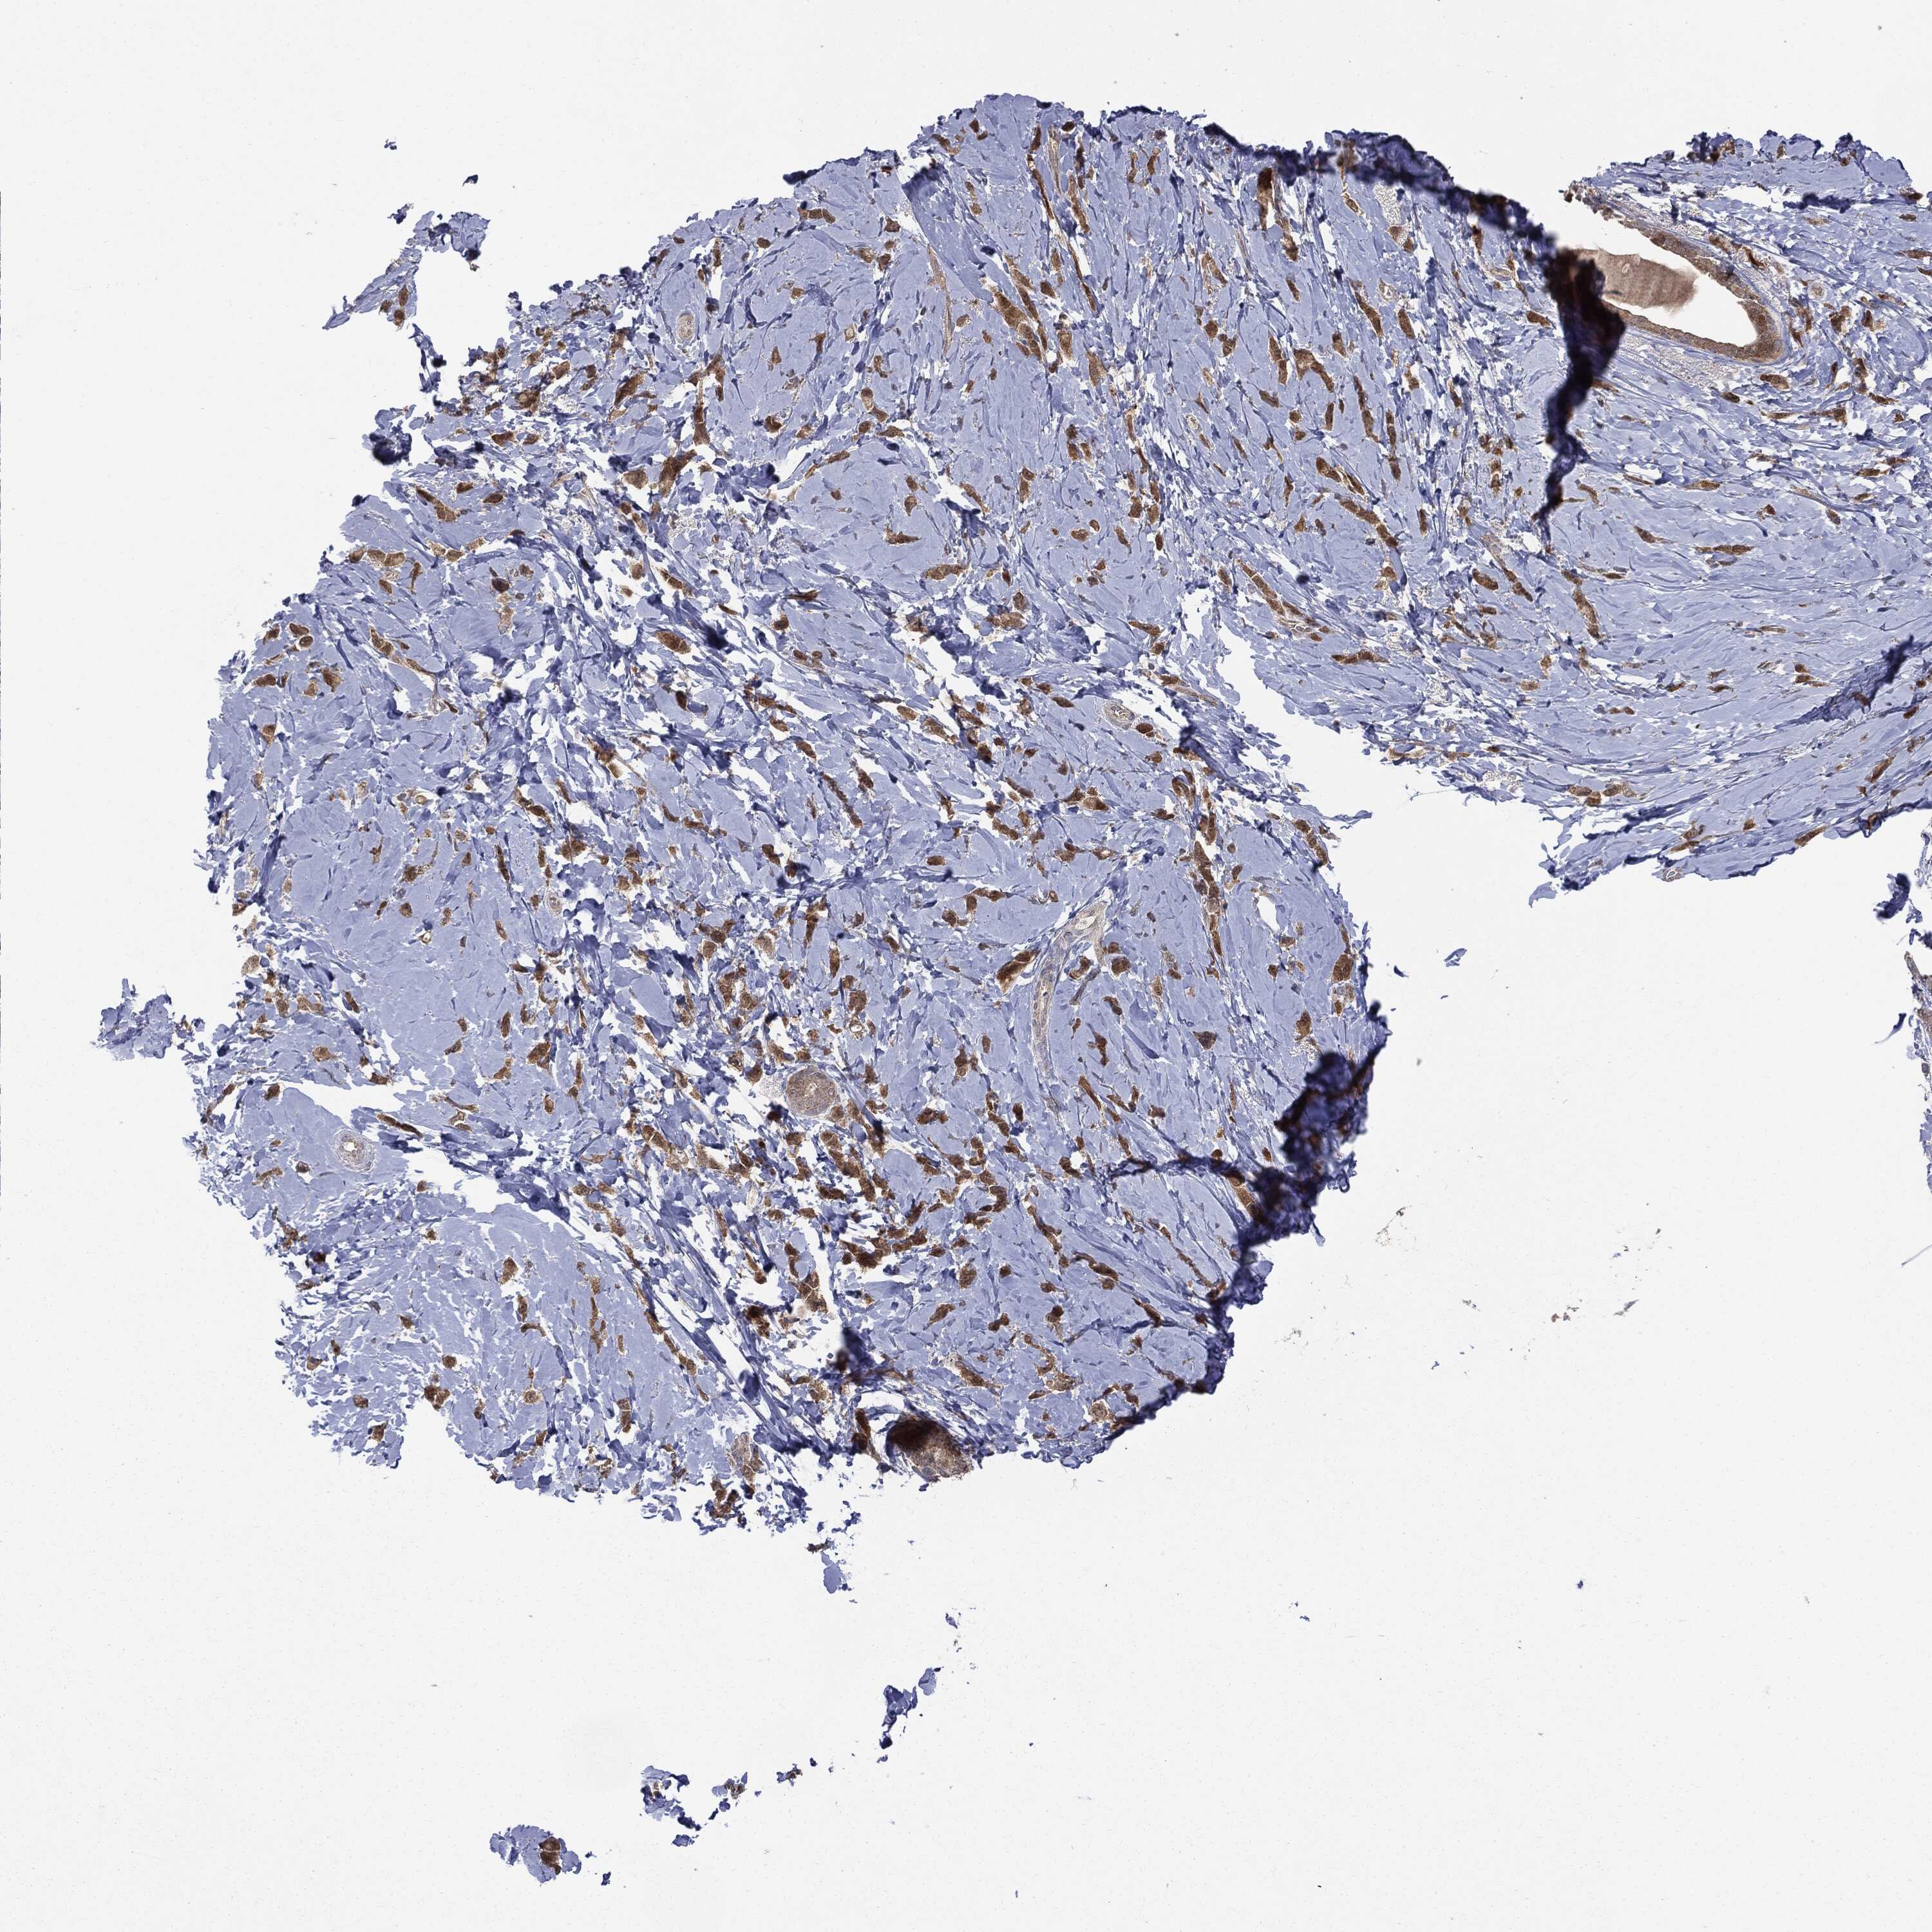

CANCER BREAST CANCER Show tissue menu

BRCA TCGA BRCA VALIDATION PROTEIN EXPRESSION

ANTIBODIES

AND

VALIDATION